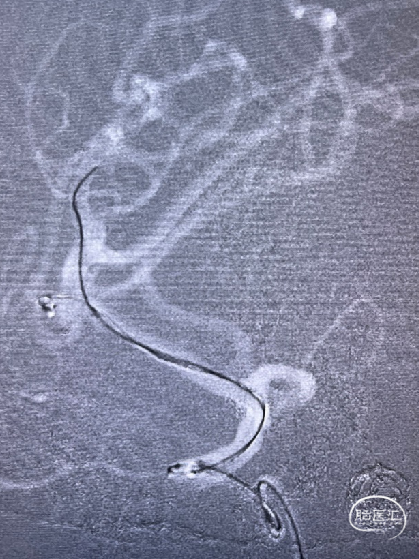

Synchro14微导丝牵引支架微导管到位;弹簧圈微导管到位。

送入3*6mm弹簧圈成篮,同时摆一根支架微导管在上干,为T型支架做准备;

释放一枚Leo baby支架 2.5*25mm。

因下干支与M1成角太锐,支架在转弯处打开,多次推拉调整,以“神龙摆尾”方式释放,将支架尾端避开上干开口。